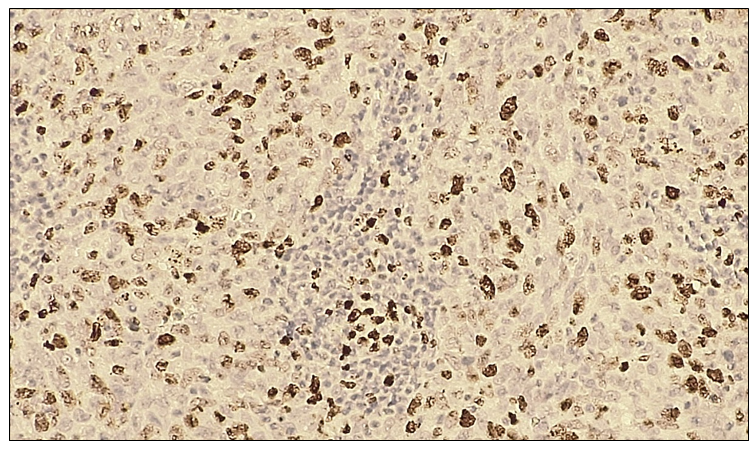

On microscopic examination, tumor cells with large-cell epithelial differentiation exhibited marked polymorphism, hyperchromatic nuclei, and numerous pathological mitotic figures. The epithelial stroma contained angiomatous blood vessels and loose fibrous connective tissue. The tumor cell nuclei demonstrated a strong positive reaction with intense dark-brown staining. | Figure 7. Moderate positive p53 immunohistochemical reaction in large cell carcinoma of the lung. IHC, DAB chromogen. Objective ×10, ocular ×40 |

In 20 patients diagnosed with large cell carcinoma of the lung, p53 marker expression was evaluated using the ALLRED scoring system. The analysis revealed weak positive expression in 5 cases (25%), moderate positive expression in 8 cases (40%), and strong positive expression in 7 cases (35%). No negative p53 expression was observed in this group.Table 8. p53 expression levels in large cell carcinoma of the lung  |